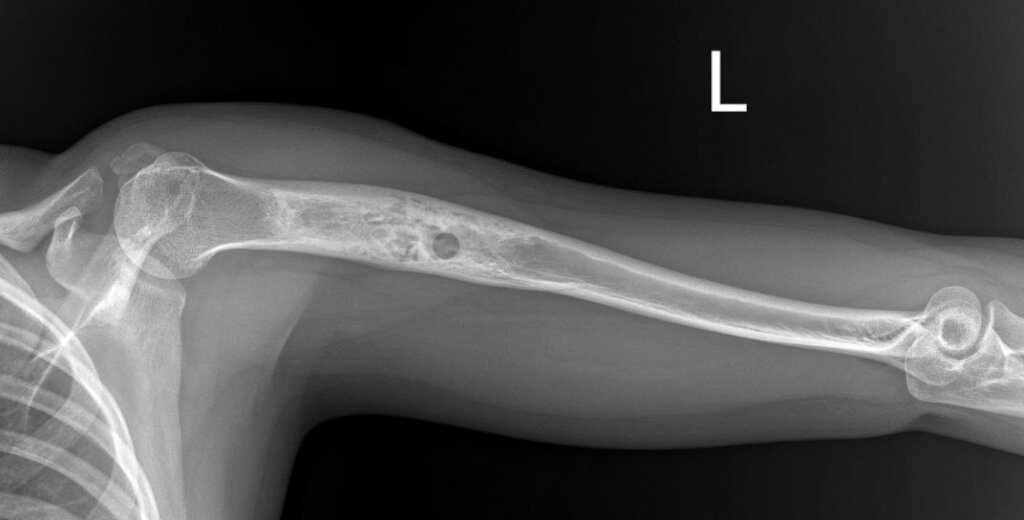

"Sasha's mother called, crying from happiness. They are now in Kyiv, just got out of the children's oncology center - Everything is fine! The oncologist studied everything from the very beginning, took another X-ray - everything is healing! Olexandra will only need to take some medication to facilitate the growth of her bone. What was thought to be a tumor is growing in the bone itself! And if it goes like this, then before the formation of a complete skeleton - by the age of 18 it should grow completely and then there will be no need for an implant! Annual check-ups, X-rays, and MRIs will continue to monitor her progress to ensure her well-being."

This miraculous turn of events has brought immense joy and relief to Olexandra's family. The family lives in Nikopol which is heavily shelled but they don't want to leave their home. Olexandra has been through two operations - one took place right after the incident and the other one was a biopsy of a tumor (21/09/2023) that turned out to be a benign formation. Now, it has become evident that her bone is regenerating naturally, eliminating the necessity for the previously planned surgery and implant.

Please find all the relevant medical documents attached below for your reference. Photos were cropped as they contained a lot of personal information.